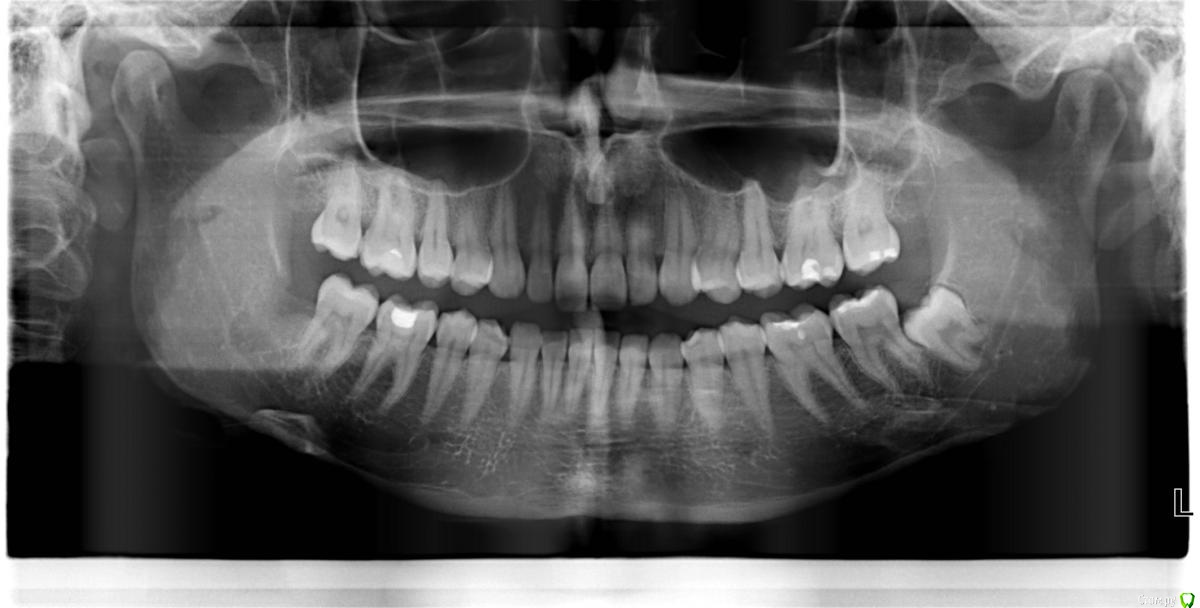

Tatyanka Опубликовано 30 ноября, 2015 Автор Поделиться Опубликовано 30 ноября, 2015 Всем доброго времени суток! С момента удаления той злостчастной восьмерки прошел год - и до сих пор время от времени возникает ноющая боль в районе удаленного зуба. Довольно слабая, но волнует само наличие неприятных ощущений - ведь что-то их вызывает спустя такое время, если есть проблема - не хотелось бы сильно запускать. Стоматолог, у которого наблюдаюсь, на снимке ничего криминального не заметил. Хотелось бы узнать ваше мнение. Извините, если я слишком мнительна. Ссылка на комментарий

shishok Опубликовано 30 ноября, 2015 Поделиться Опубликовано 30 ноября, 2015 Лунка зажила хорошо.Криминала действительно нет.Не переживайте. Ссылка на комментарий

red_butler Опубликовано 30 ноября, 2015 Поделиться Опубликовано 30 ноября, 2015 Проверить бы на витальность 1.6 и 4.6 Ссылка на комментарий